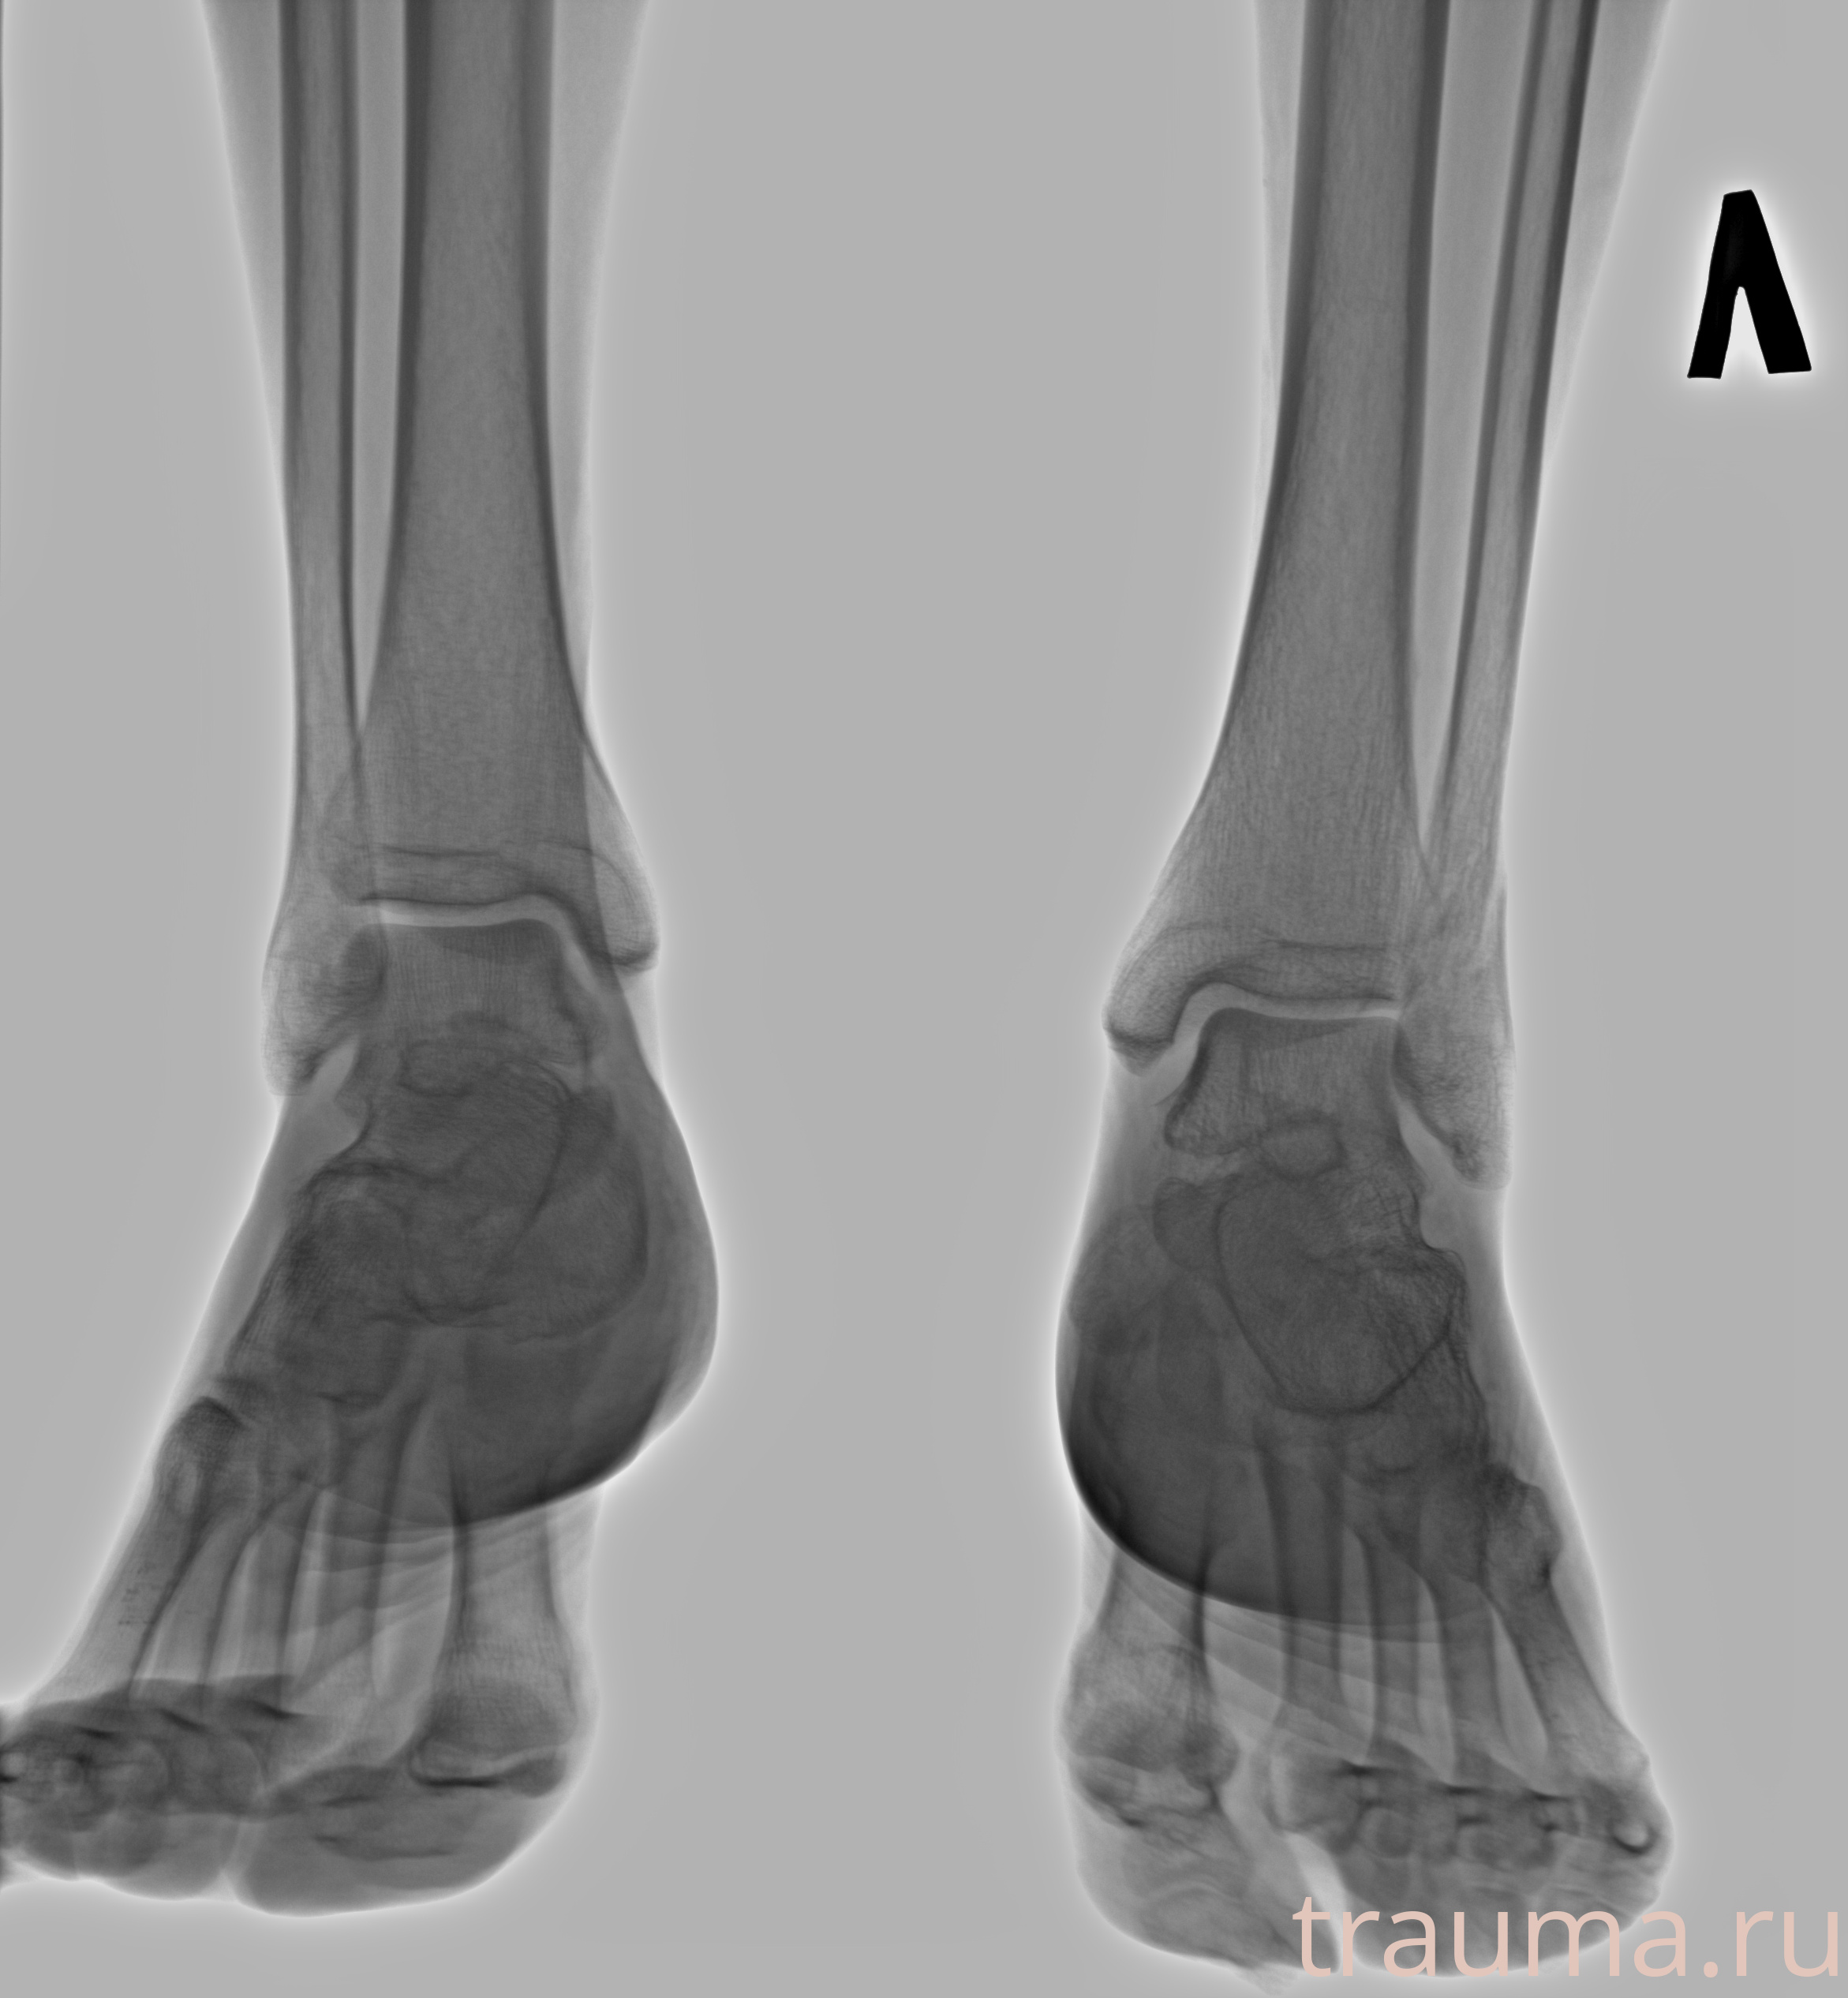

Рентгенограммы

Рентген на дому: по вашему адресу приезжает врач-рентгенолог, травматолог-ортопед с мобильным рентгеновским аппаратом, проводит диагностику травмы или заболевания, делает необходимые рентгенограммы, дает рекомендации по дальнейшему лечению. Получить качественные снимки в домашних условиях возможно благодаря уникальной методике, разработанной МосРентген Центром для института  Склифосовского